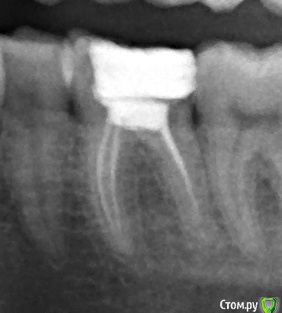

Ангеланя Опубликовано 12 февраля, 2015 Поделиться Опубликовано 12 февраля, 2015 Здравствуйте! Помогите пожалуйста, я не знаю что делать, мне очень нужен совет.Проблема с зубом 3.6 возникла еще в 2004 году, он у меня разрушился (во время беременности), лечили очень долго - закладывали мышьяк, удаляли нервы, поставили обычную пломбу, с которой я проходила 8 лет! Пломба выпала в 2012. Я заменила ее на световую, не помню точно, но каналы вроде тоже перепломбировывали. Прикрепляю снимок, сделанный через пол года после перепломбировки. Зуб меня не беспокоил, ходила я с новой пломбой 2 года. Но недавно откололся кусочек и мне острый край создавал дискомфорт, пошла к стоматологу.Пошла в частную клинику, работающую по ОМС.Значит пломбу она вскрыла, стала тыкать - мне больно, поставила 3 или 4 укола, говорит, что стал виден у соседнего зуба поверхностный кариес, лечила вроде как его, световую пломбу накладывала. Я не знаю что конкретно она делала. В завершении она наложила мне временную пломбу, и сказала, что этот зуб идет под коронку, смысла его вновь пломбировать нет, я с ней согласилась, мне до нее уже об этом говорили. На следующий день прихожу к ортопеду, он отправил на снимок, посмотрев его, сказал,что нужно перелечивать канал, к тому же он видит воспалительный процесс. Прихожу я к терапевту, уже к другому, в другую клинику, платную. Она посмотрела мои снимки и просто ошарашила меня - зуб подлежит удалению!!!!!! Отсутствует бифуркация, следовательно будет воспалительный процесс периодонта. Коронка противопоказана, и постоянная пломба тоже, т.к. через несколько месяцев зуб разрушится окончательно. Она позвала ортопеда (другого), та подтвердила ее мнение, и высказала недоумение, почему ортопед, который меня смотрел до этого не заметил.В-общем я в пребываю в шоке. Зуб терять не хочу. Посоветуйте пожалуйста,что можно сделать в этой ситуации, для меня очень важно сохранить этот зуб. Я подозреваю, это врач при вытаскивании пломбы повредила зуб. Сравните снимки - мои подозрения подтверждаются? Я хочу поехать в ту клинику и написать претензию, ведь из-за ее неосторожных действий я потеряю зуб. Что мне можно потребовать, может компенсацию? Посоветуйте, а стоит ли вообще разбираться, ведь зуб не вернешь. Или все-таки можно хоть что-то сделать? Так хочется, чтоб доктор у которой я сегодня была ошибалась! еще раз напомню, на первом фото - снимок 2012 года, на втором - сегодняшний день с временной пломбой. Ссылка на комментарий

shishok Опубликовано 12 февраля, 2015 Поделиться Опубликовано 12 февраля, 2015 Возможно и нет перфорации(угол съёмки другой).КТ в помощь.Но мне не нравится разрушение задней стенки ниже уровня десны.ИМХО. Ссылка на комментарий

Гарриевич Опубликовано 12 февраля, 2015 Поделиться Опубликовано 12 февраля, 2015 Для начала прекратите сыпать обвинениями на всех подряд. Первый снимок сделан в прямой проекции, а второй под углом сверху, отсюда и разница. На последнем снимке вообще ничего не видно, он не информативен. Хотите разобраться и быть уверенной идите к хорошему доктору, тут на форуме есть несколько докторов с Вашего города 1 Ссылка на комментарий